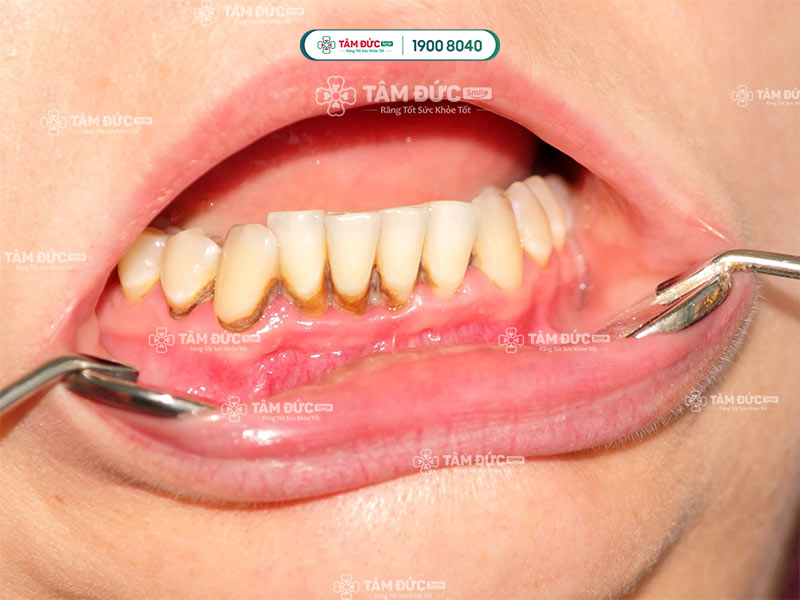

Cao răng tích tụ lâu ngày dẫn đến sâu viêm

Trước khi giải đáp vấn đề lấy cao răng mất bao lâu, Quý khách cần biết lợi ích khi lấy cao răng định kỳ là gì. Lấy cao răng là một thủ thuật nha khoa giúp loại bỏ mảng bám và cao răng tích tụ trên răng và nướu. Mảng bám là một lớp màng dính, vô hình bám trên răng sau khi ăn uống. Nếu không được loại bỏ, mảng bám sẽ cứng lại và trở thành cao răng. Cao răng là một lớp cứng, màu vàng hoặc nâu bám trên răng và nướu.